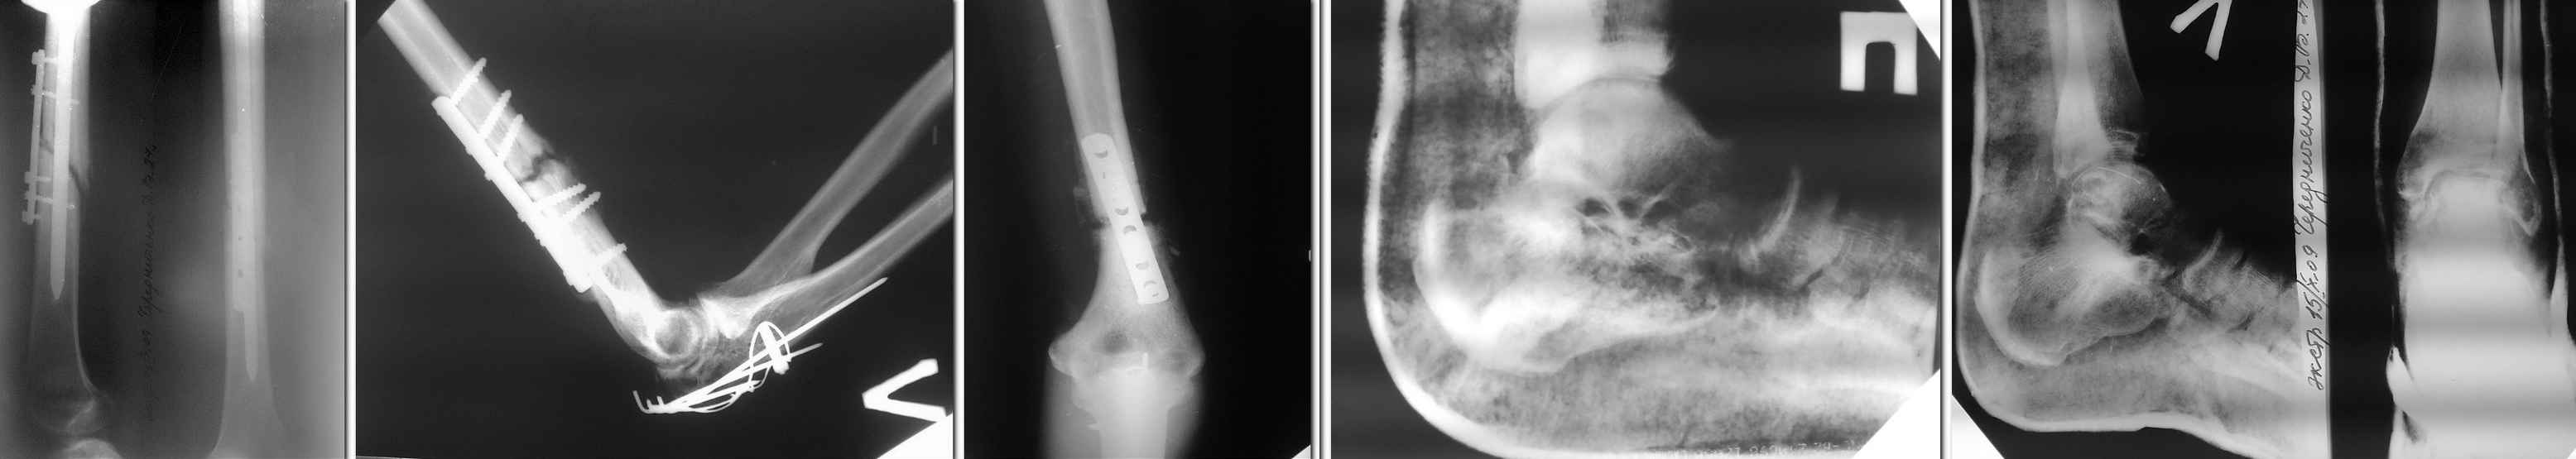

Уважаемые коллеги! Будем признательны любому совету в отношении тактики лечения пациента Ч. 27 лет, поступившего в наше отделение для этапного лечения по поводу сочетанной травмы, полученной 19.07.2009 в ДТП.

Оперирован в другом лечебном учреждение 05.08.09- остеосинтез левой бедренной кости, левой плечевой кости, левого локтевого отростка, трансартикулярная фиксация спицами левой таранной кости, выполнена закрытая репозиция перелома правой пяточной кости гипсовым лангетом. В настоящее время признаки консолидации левой бедренной и левой плечевой костей выражены слабо, имеются контрактуры левых локтевого и коленного суставов, спицы удалены продолжается иммобилизация стоп.Мнения коллег по дальнейшей тактике лечения разошлись:- выполнить реостеосинтез бедренной и плечевой костей;- продолжать консервативное лечение в надежде на консолидацию переломов, поскольку оперативное пособие не приведёт к более ранней активизации больного из-за имеющихся переломов костей стоп и верхней конечности.Заранее спасибо.

Cо дня операции (а именно с этого дня нужно отсчитывать срок сращения) прошло чуть больше 2-х месяцев. Выбрали наиболее травматичные способы репозиции и фиксации.За это время не приходится

рассчитывать на сращение даже при изолированных переломах. А при множественных - тем более. Признаки образования костной мозоли имеются. Не исключено, что это выльется в ложный сустав (на плече такая вероятность больше, судя по снимкам) - тогда спокойно и прооперируете. Не нужно выполнять повторную операцию только потому, что предыдущую сделали не так, как сделали бы вы.

Обсуждать каческтво остеосинтеза не хочется, что выросло то выросло. Но в последние годы все чаще приходится видеть такие результаты. Распространение металлоконструкций делает свое дело. Оба перелома с дистазами м/у отломками, так, что ждать сращения не приходится. Безусловно показан реостеосинтез, способ в зависимости от возможностей и традиций клиники.

Мы малоинвазивно (насколько возможно) убрали бы пластины и стержень из бедра, и закрыто пересинтезировали стержнями с блокированием. Операции не самые травматичные и сложные. Результатом будет немедленное "хирургическое сращение", т.е. восстановление полной опороспособности и создание условий для безопасной функциональной реабилитации.

Перспектива сращения в нынешнем положении как минимум очень отдаленная и попросту сомнительная.

Доброе время суток. Влад - решать Вам, ведь только Вы несете ответственность за больного. Я бы на вашем месте поступил так: плечо-замена метода(блок.стержень); олекранон - не трогал бы, а дал ЛФК и Физиотерапию;бедро - замена метода(блок.стержень);а таран - дал бы осевую нагрузку 30%-40% в гипсе, а через 2 недели посмотрел бы. Ведь самое главное восстановить функцию конечностей. Но, повторюсь - решать Вам, и только Вам.